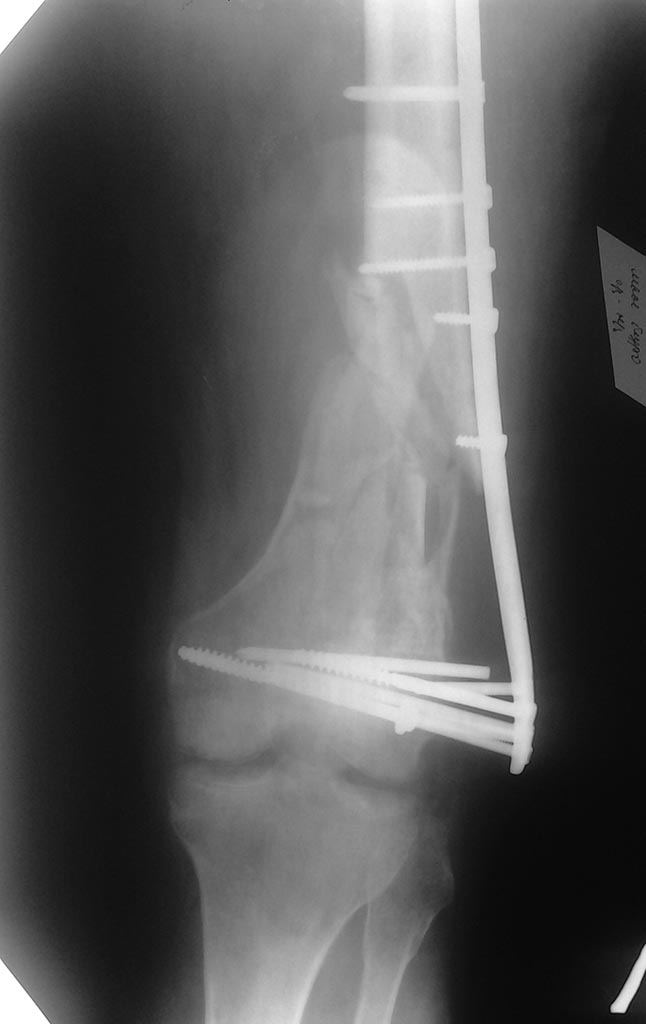

Несостоятельность фиксации пластиной дистального отдела бедра

Уважаемые коллеги! Прошу помощи в выборе метода операции. Больному 64 года, пострадал в ДТП в декабре 2013 года в ДТП. Множественная травма: сегментарный перелом правой локтевой кости,оскольчатый перелом левой бедренной кости в нижней трети, перелом обеих лодыжек левой голени.

Операции МОС перелома костей предплечья пластинами, МИПО перелома бедра пластиной, мос лодыжек. Через 4 мес на костылях оступился, произошла полная нагрузка на ногу, одномоментно возникла деформация бедра. На данный момент обсуждаются 2 варианта операции (с учетом предположительно неудовлетворительного состояния губчатой ткани в мыщелках бедра:

1) удаление фиксаторов, ретроградно БИОС с костной аутопластикой зоны перелома (Интерлок, дистальное блокирование 1 спиральным винтом 12 мм и двумя 6 мм в разных плоскостях)

2) удаление фиксаторов, более длинная аналогичная пластина с угловой стабильностью, наложенная по принципу "шинирования", в проксимальном отделе фиксировать 4-мя винтами в значительном удалении от перелома, в дистальном отделе расположить чуть ниже, костная аутопластика.Заранее спасибо за конструктивную критику и советы.